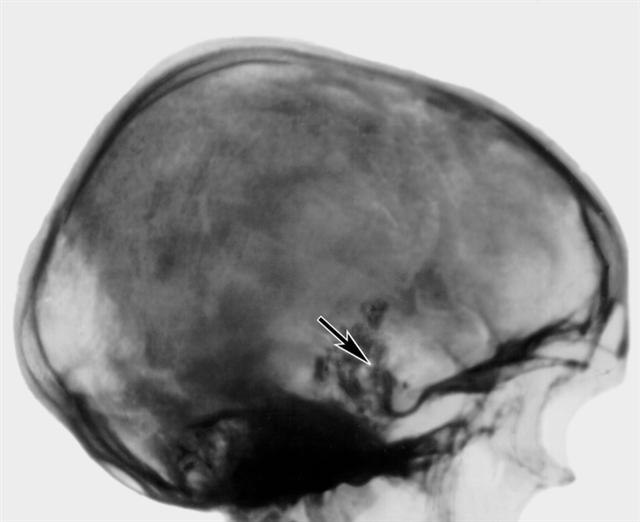

Рис. 13. Боковая рентгенограмма черепа больного с хордомой основания черепа без признаков гипертензии: обширный коралловидный петрификат на скате и ретросупраселлярно (указан стрелкой).